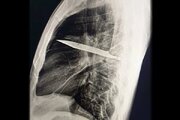

عجیب اما واقعی؛ چاقوی بزرگی که ۱۰سال در سینه یک مرد فرو رفته بود و نمیدانست + عکس

در یکی از نادرترین موارد پزشکی ثبتشده، مردی ۴۴ ساله اهل تانزانیا با ترشح چرک از قفسه سینهاش به اورژانس مراجعه کرد؛ اما آنچه پزشکان کشف کردند، فراتر از انتظار بود.